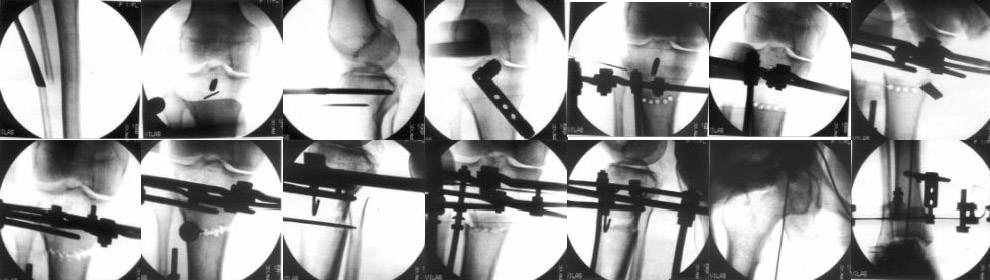

Картинки - в приложении.Будут вопросы - готов ответить.

|

Ещё картинка - схема. Хотя у Соломина всё написано.

Вот ещё картинки, которые отправлял в Ортопод. Коррекция кривизны и удлинение на 3 см.

Затеется дискуссия - буду счастлив.

Удачи всем.

Александр Артемьев